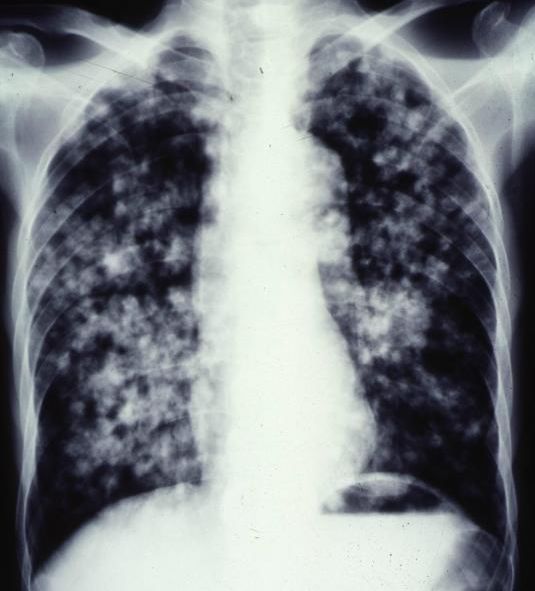

1. 一位37歲女性一個月來呼吸困難逐漸明顯,胸部X光如圖所示,應先採取下列何種處置?

(A) 先抽胸水(30-50ml)送檢 (B) 放引流管將水一次抽完並送檢 (C) 做胸部電腦斷層,看是否有腫瘤 (D) 做肋膜生檢(切片)送病理學檢查 (E) 先試用2-3天的口服利尿劑